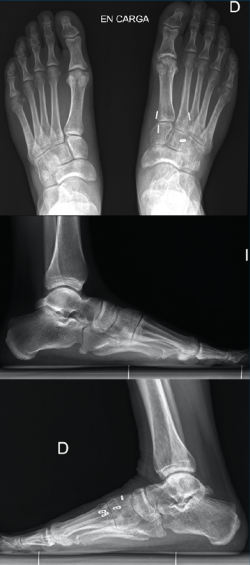

La revisión a los 3 meses mostró resultados satisfactorios en ambos casos, con tolerancia de la carga completa. Además, las imágenes radiológicas demostraron el mantenimiento de la reducción conseguida en el quirófano, sin movilización del material (Figuras 5 y 6).

Figura 6. Resultados radiográficos posquirúrgicos en el caso 2.

En el primer caso, la incorporación laboral fue a los 4 meses y, en el segundo caso, a los 6 meses; los pacientes no presentaron dolor. A los 10 meses postoperatorios el examen clínico no reveló evidencia de dolor en la zona quirúrgica y los pacientes habían reanudado todas sus actividades regulares, incluida la práctica deportiva, sin complicaciones. Además, las radiografías en ese momento revelaron una reducción anatómica de la lesión.